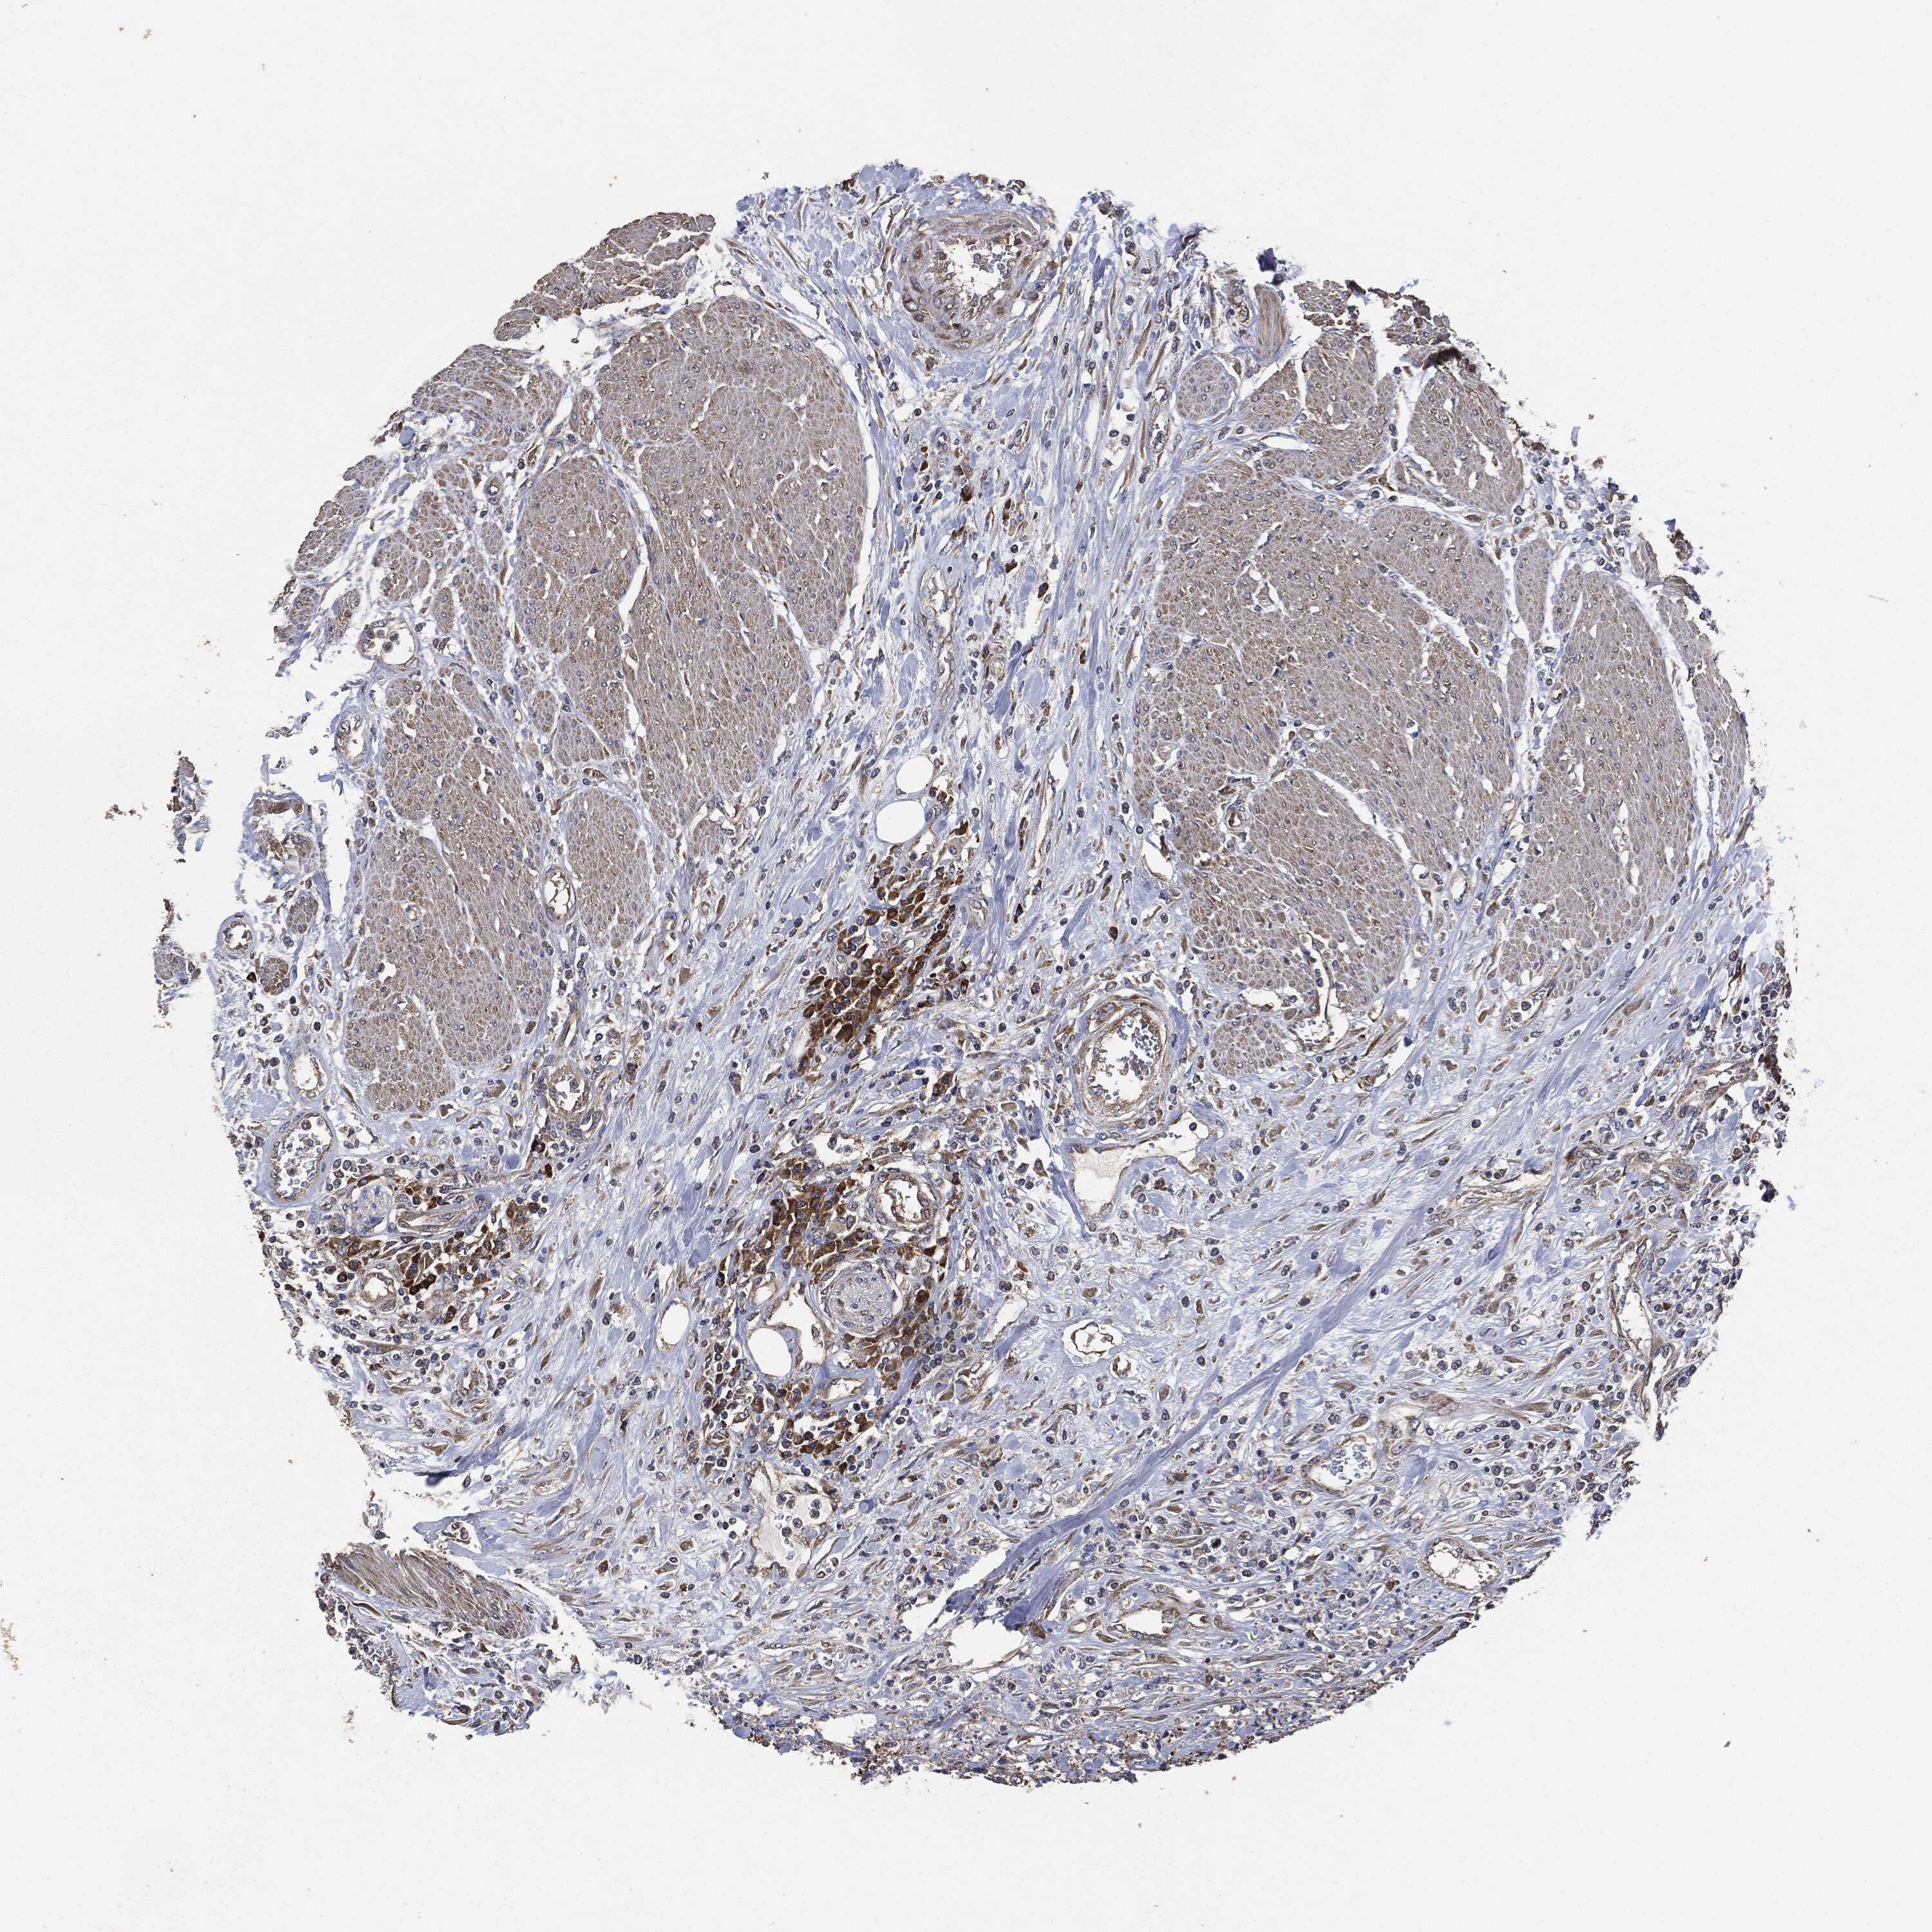

UROTHELIAL CANCER - Protein expressioni

A mouse-over function shows sample information and annotation data. Click on an image to view it in a full screen mode. Samples can be filtered based on level of antibody staining by selecting one or several of the following categories: high, medium, low and not detected. The assay and annotation is described here.

Antibody stainingi

Antibody staining in the annotated cell types in the current human tissue is reported as not detected, low, medium, or high, based on conventional immunohistochemistry profiling in selected tissues. This score is based on the combination of the staining intensity and fraction of stained cells.

Each image is clickable and will lead to virtual microscopy that enables deeper exploration of all samples and also displays staining intensity scores, fraction scores and subcellular localization as well as patient and tissue information for each sample.

Antibody HPA073281

Antibody CAB025316

Staining

High

Medium

Low

Not detected

Intensity

Strong

Moderate

Weak

Negative

Quantity

>75%

75%-25%

<25%

None

Location

Nuclear

Cytoplasmic/membranous

Cytoplasmic/membranous,nuclear

Urothelial carcinoma, High grade